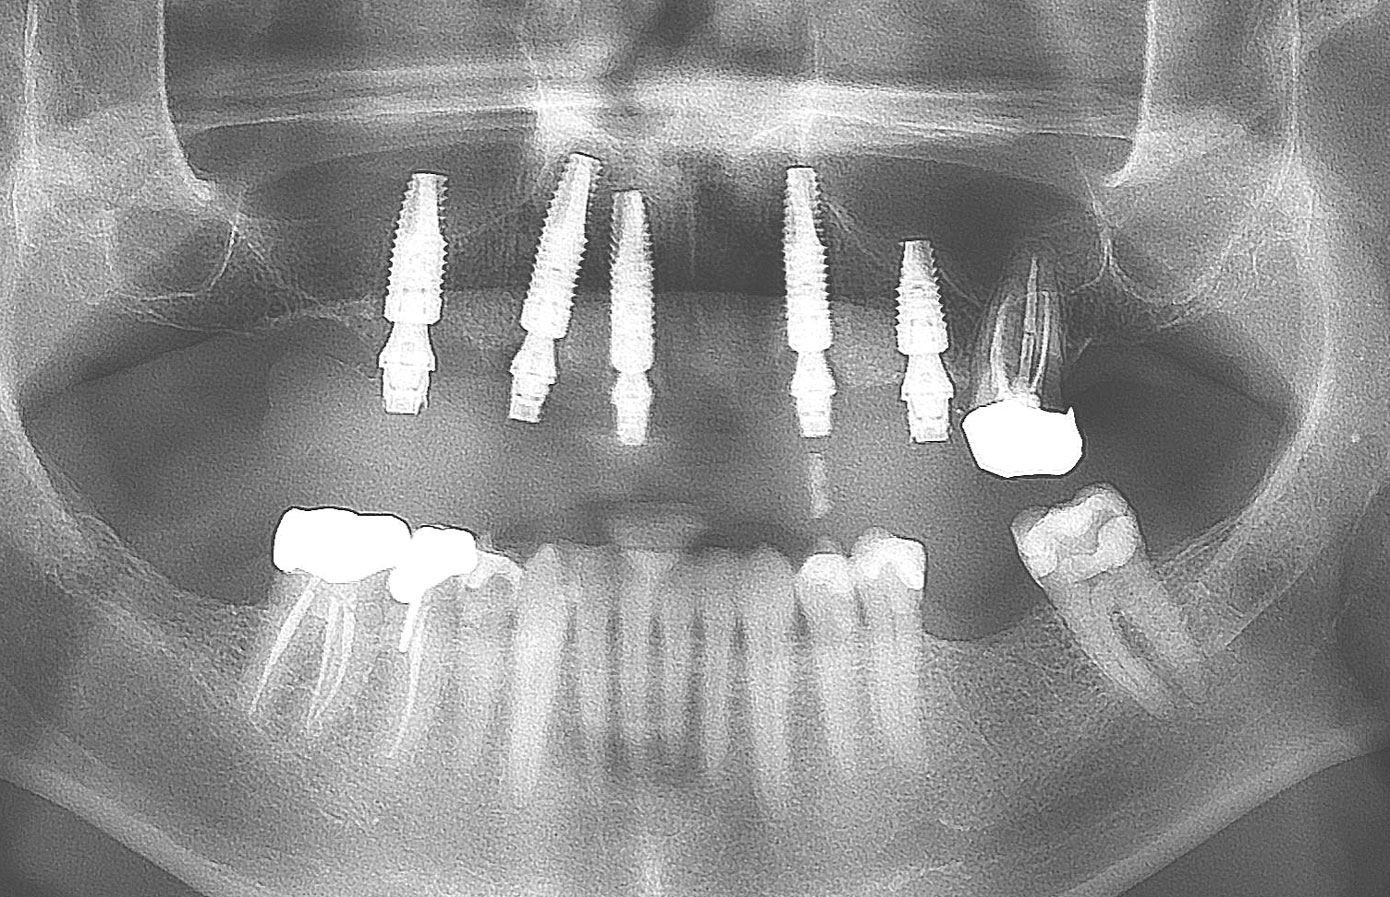

At the initial visit, a panoramic x-ray (Figure 11) and periapical x-rays were taken. The patient was photographed to capture her full face and shoulders, and a digital scan of the maxillary dentition was obtained. This file was electronically sent to the implant company to complete the VSD.

Fig 11. Initial panoramic radiograph.

Figure 11

Fig 21. Postoperative panoramic radiograph on the day of surgery.

Figure 21

Fig 22. Postoperative periapical x-rays on the day of surgery demonstrating the provisional restoration with ti-bases fully seated to multi-unit abutments and ideal immediate implant placement.

Figure 22

Fig 24. Initial panoramic radiograph.

Figure 24

Fig 40. Postoperative panoramic radiograph on the day of surgery.

Figure 40